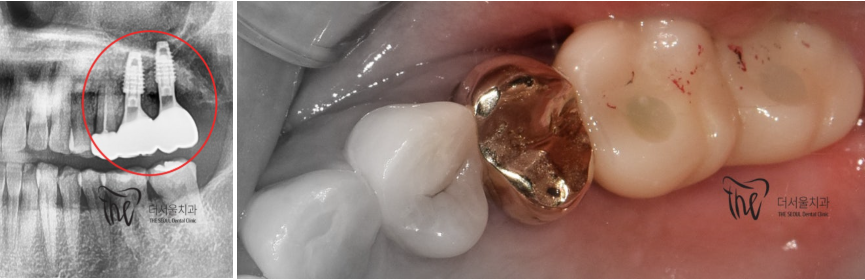

『치료 종료』

자연치아만큼은 아니지만,

그래도 튼튼한 새 치아가 만들어졌습니다.

단순히, 금니 통증 에 따라서 치과에

내원을 하셨는데 이렇게 소수술이 진행 될 지는

그 누구도 알 수 없었을겁니다.